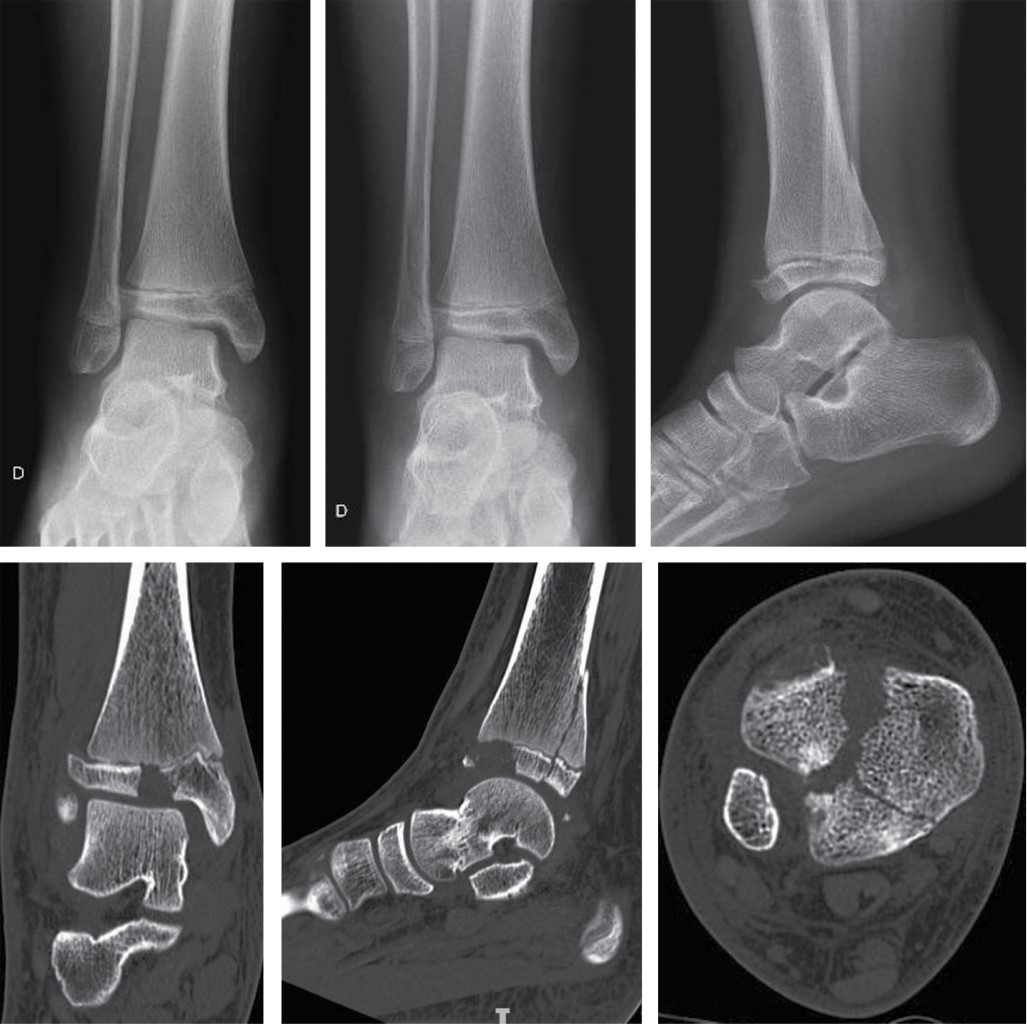

Figure 1

Figure 2

Figure 3

Figure 4

Figure 5